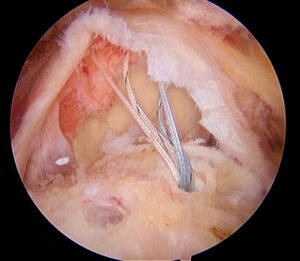

En una entrada anterior del blog hablábamos acerca de la inestabilidad de hombro, sus aspectos generales, y cómo era importante identificar si había un defecto de hueso asociado. En estas

El hombro es la articulación más móvil del cuerpo. Debido a su peculiar anatomía, en la que la superficie articular de la glenoides es mucho más pequeña que la cabeza